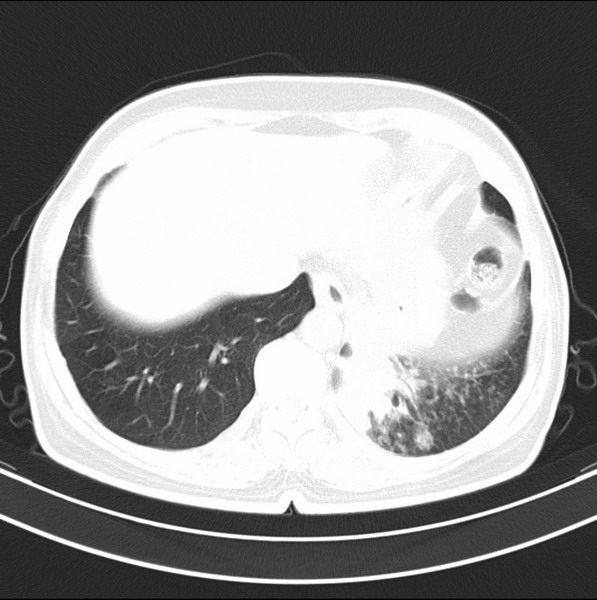

女、63

咳嗽、胸痛四个月

支持左下中央型肺癌伴阻塞性炎症不张。

包绕左下肺基底段的不规则的软组织肿块,段支气管腔变形、狭窄及阻塞性炎症,病变区不规则强化,又是老年女性支持楼上看法。

考虑左肺下叶中央型肺癌伴阻塞性肺炎、支气管黏液嵌塞。

典型病例:左下肺基底段中央型肺癌,相应支气管狭窄并阻塞性炎症